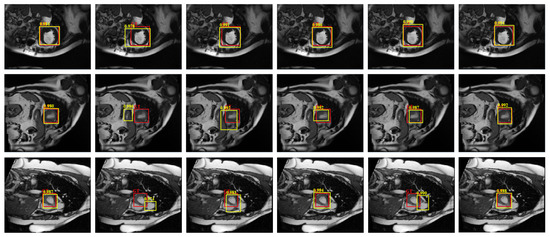

4.4.1. Detection Performance